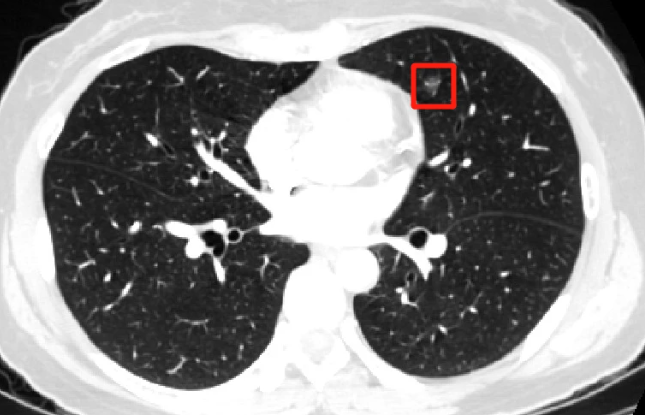

肺结节病因复杂,临床表现缺乏特异性,因此医生诊断有一定难度。近年来,随着螺旋CT的日益普及,结节病变的检出率明显提高。临床上,把肺实质内小于等于3cm的病灶(需除外肺不张和肿大的淋巴结)称为结节,大于3cm的病灶称为肿块,而小于1cm的结节称为小结节,小于5mm的结节称为微小结节,之所以这样定义,是因为大于3cm的病灶多为恶性,而更小的病灶可能是良性或恶性,结节的大小与结节的良、恶性间具有相关性,小的结节,良性可能性大,有资料报道超过2000例小于4mm的微小结节,无一例属于恶性。

(4) 结节大小在1公分以上,伴有毛刺样、分叶状或毛玻璃样、胸膜凹陷等改变的。

现在胸部X线和CT检查是诊断胸部疾病最常用的手段。胸部CT体检中肺部小结节的发生率高达约10%-20%,发现率远高于X线检查。由于CT具有X线无法比拟的优势,它具有高分辨力,并且为横断位图像,可以避免肋骨、脊柱、心脏的阻挡而清晰的观察肺组织。X线胸片敏感性则相对较差,发现肺癌多数已经中晚期,并常有假阳性,约有30%左右X线胸片报告的肺部结节为假阳性,即没有病灶而是伪影。放射科诊断医师主要是根据小结节的大小、形态、密度、有无钙化、周围有无卫星病灶,边缘有无分叶、毛刺、胸膜凹陷等情况来判断小结节的良恶性,目前诊断准确率可达到95%以上,胸部CT目前被公认为是诊断肺部小结节的最佳检查手段。

小结节的性质多种多样,良性的包括炎性假瘤、错构瘤、结核球、局限性纤维化、局限性慢性炎症等,癌前期病变为不典型腺瘤样增生,恶性的则可能是原发性肺癌或肺内转移癌。